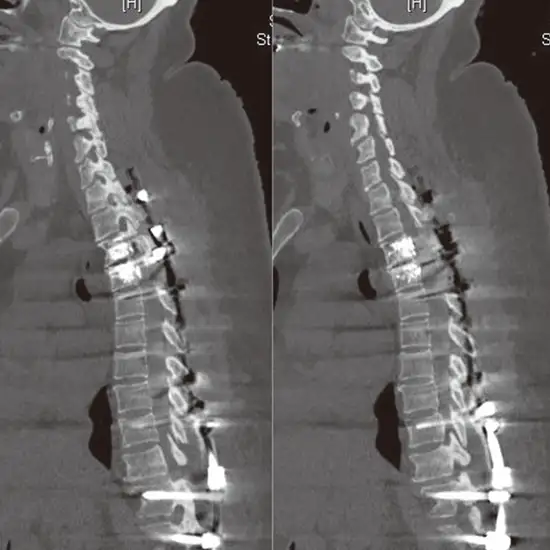

NCCT (Non-Contrast Computed Tomography) Dorsal Lumbar Spine is an imaging procedure used to create images of the lumbar region of the vertebral column. The procedure creates the image of the spinal column, the vertebral bones, intervertebral disks, and the surrounding soft tissues.

The patient will be instructed to lie straight and still on a movable examination table attached to the CT machine for the NCCT dorsal lumbar spine. The table will slide into the machine for the scanning procedure. The X-rays from the machine will capture an image of the dorsal lumbar spine and the surrounding areas.